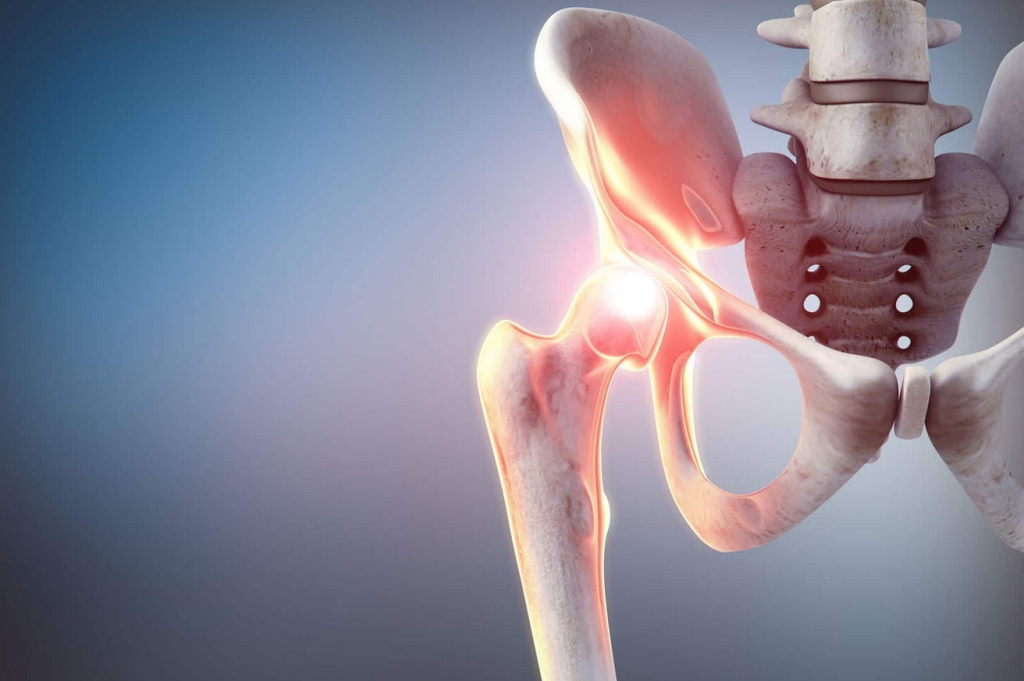

Чаще всего пожилым людям выполняется эндопротезирование – замена повреждённого участка искусственным суставом. Операция при переломе шейки бедра проводится под спинальной анестезией и длится не больше полутора часов. Благодаря современным методам можно сделать минимальный разрез, что серьёзно снижает травматичность вмешательства.

Если операцию при переломе проводить нельзя (например, при наличии тяжёлых сопутствующих заболеваний), применяют консервативное лечение с наложением гипса и скелетным вытяжением. Но такой путь более длительный и сопряжён с большим риском осложнений.